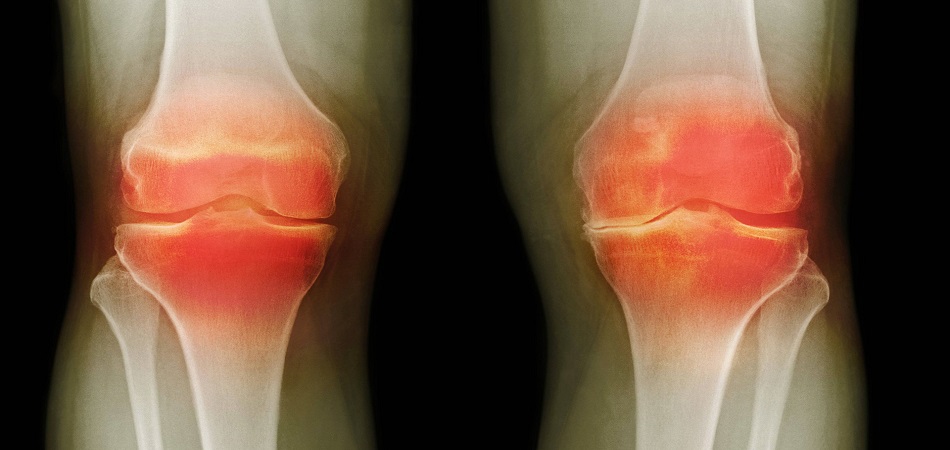

Voici les résultats des personnes qui ont participé aux tests de Marukaya Cream :